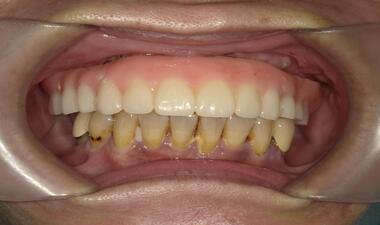

術後

裝戴固定

Full Arch 上顎假牙